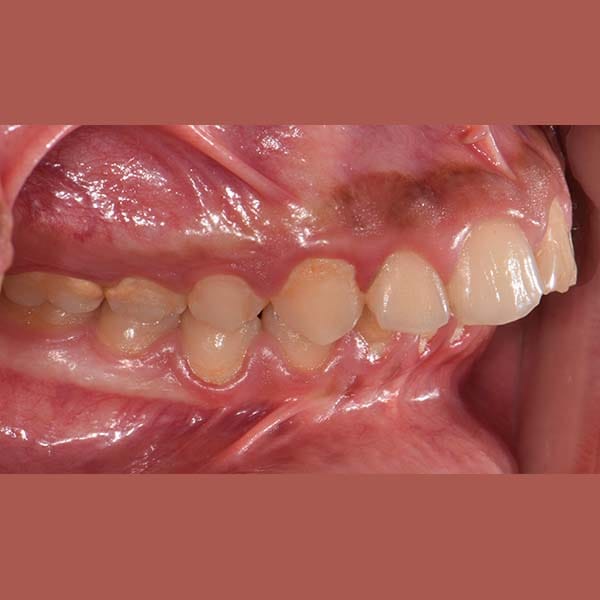

BEFORE

عانى هذا الشاب اليافع من بروز في الأسنان الأمامية العلوية بسبب تراجع الفك السفلي. أثرت هذه المشكلة على قدرته على قطع الطعام بشكل جيد، بالإضافة إلى شعوره بالخجل من الابتسام أمام أصدقائه في المدرسة.